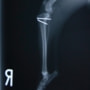

■ 症例20 ポメラニアン 8ヶ月 1.8kg

左右膝蓋骨脱臼 グレードⅢ

2ヶ月前から間欠的跛行が認められ、両膝の膝蓋骨脱臼整復術を行った。

手技は縫工筋及び内側広筋の解放、脛骨粗面の外側転位、滑車ブロック形造溝術、内外側関節包の縫縮を選択し実施した。

右側の膝蓋骨脱臼は上記手技で整復されたものの、左側はそれのみでは膝蓋骨が浮く様子が認められた。その為、PDS縫合糸にて膝蓋靱帯を1糸のみ縫合し、靱帯の縫縮を行った。